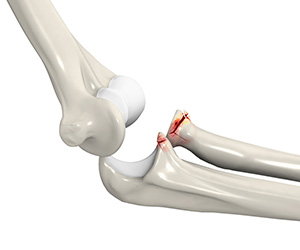

Elbow Fracture Reconstruction

Elbow fracture reconstruction is a surgical procedure employed to repair and restore the appearance and full function of a damaged elbow caused by severe trauma or injury.

Elbow (Olecranon) Fractures

Olecranon fractures are described as a break in the bony tip of the elbow that sticks out when you bend your arm.

Radial Head Fractures of the Elbow

Radial head fractures are very common and occur in almost 20% of acute elbow injuries.

Coronoid Fracture of the Elbow

A coronoid fracture is a break in the coronoid process which is a bony prominence of the ulna bone in the elbow joint.